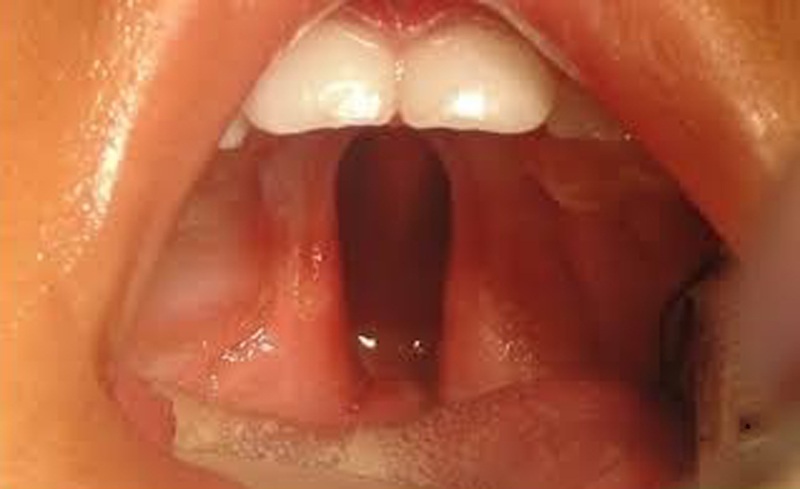

Piensa en el paladar no como una simple pared, sino como un piano de alta precisión. Su función al hablar es increíble: debe moverse con rapidez y elevarse para tocar la parte trasera de la garganta, sellando la nariz.

Esto es lo que nos permite pronunciar sonidos explosivos como la "p", la "b", la "t", o la "d". Sin ese sellado, el aire se escapa por la nariz y el habla suena nasal, como si siempre estuviéramos resfriados. La cirugía repara la estructura, construye ese "techo" y da al músculo la oportunidad de funcionar.

FOTO: (Web maxilopediatrico.blogspot)